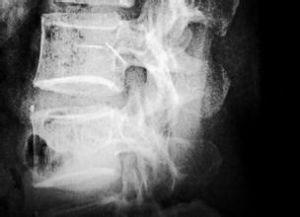

腰脫突出的髓核止於後縱韌帶前方稱為“突出”,而穿過後縱韌帶進入椎管內的,稱為“脫出”。根據髓核向後突出部位分為3型:

1.後外側方突出型:纖維環的後方最弱的部位在椎間盤中線兩側,此處本身薄弱,同時缺乏後縱韌帶的強力中部纖維的支持,因此是腰椎間盤突出最常見的部位。臨床上最為多見,約占80%左右。

2.中央突出型:指髓核通過纖維環後部中央突出,達到後縱韌帶下。除引起坐骨神經症狀外,還可刺激或壓迫馬尾神經,表現為會陰部麻痹及大小便障礙。

3.椎間孔內突出型和極外側型:指髓核向後經後方的纖維環及後縱韌帶突入椎管,進入椎間孔內,容易漏診,但所幸其發生率低,僅1%左右。